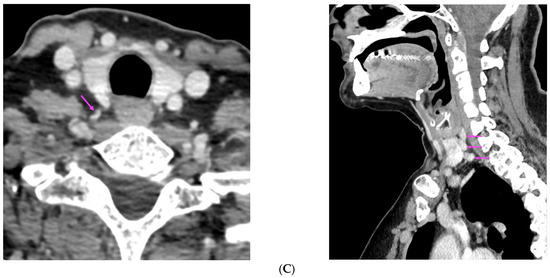

| Reference | Imaging Evaluation | Pathology Report |

|---|---|---|

| [37] | US: six nodules of 5 mm to 16 mm located subcutaneously anterior of right sternocleidomastoid muscle 99m-Tc sestamibi scintigraphy: no hyper-functional foci CT: similar to US | Parathyromatosis |

| [38] | 99m-Tc-MIBI imaging (SPECT/CT): three foci of elevated uptake on early phase with slow washout on delayed phase | Hyperplastic parathyroid tissues |